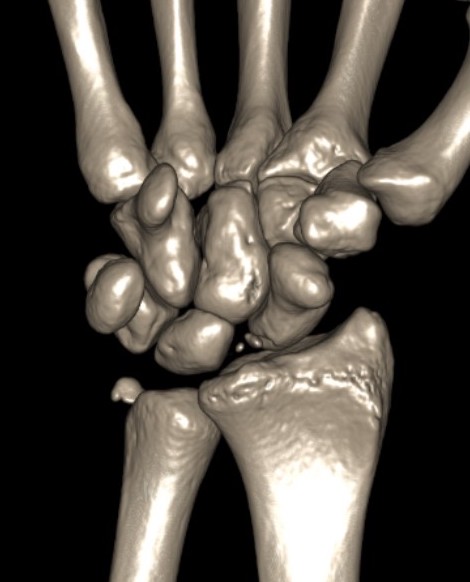

Radial styloid + dorsal rim fractures